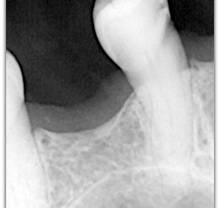

What represent the white, blue, red or black areas which can been seen on the tooth?

According to the pathologies of the tooth (destructured enamel, affected dentine, anfractuous fissure, presence of a crown…), the signal of fluorescence of the dentine will be different (weaker, darker, redder, absent…)

Why is the tooth green on the screen?

The spectrum of the signal of fluorescence (let’s call it "its color") is rather in the green when the dentine is healthy and red/dark when the dentine is infected.